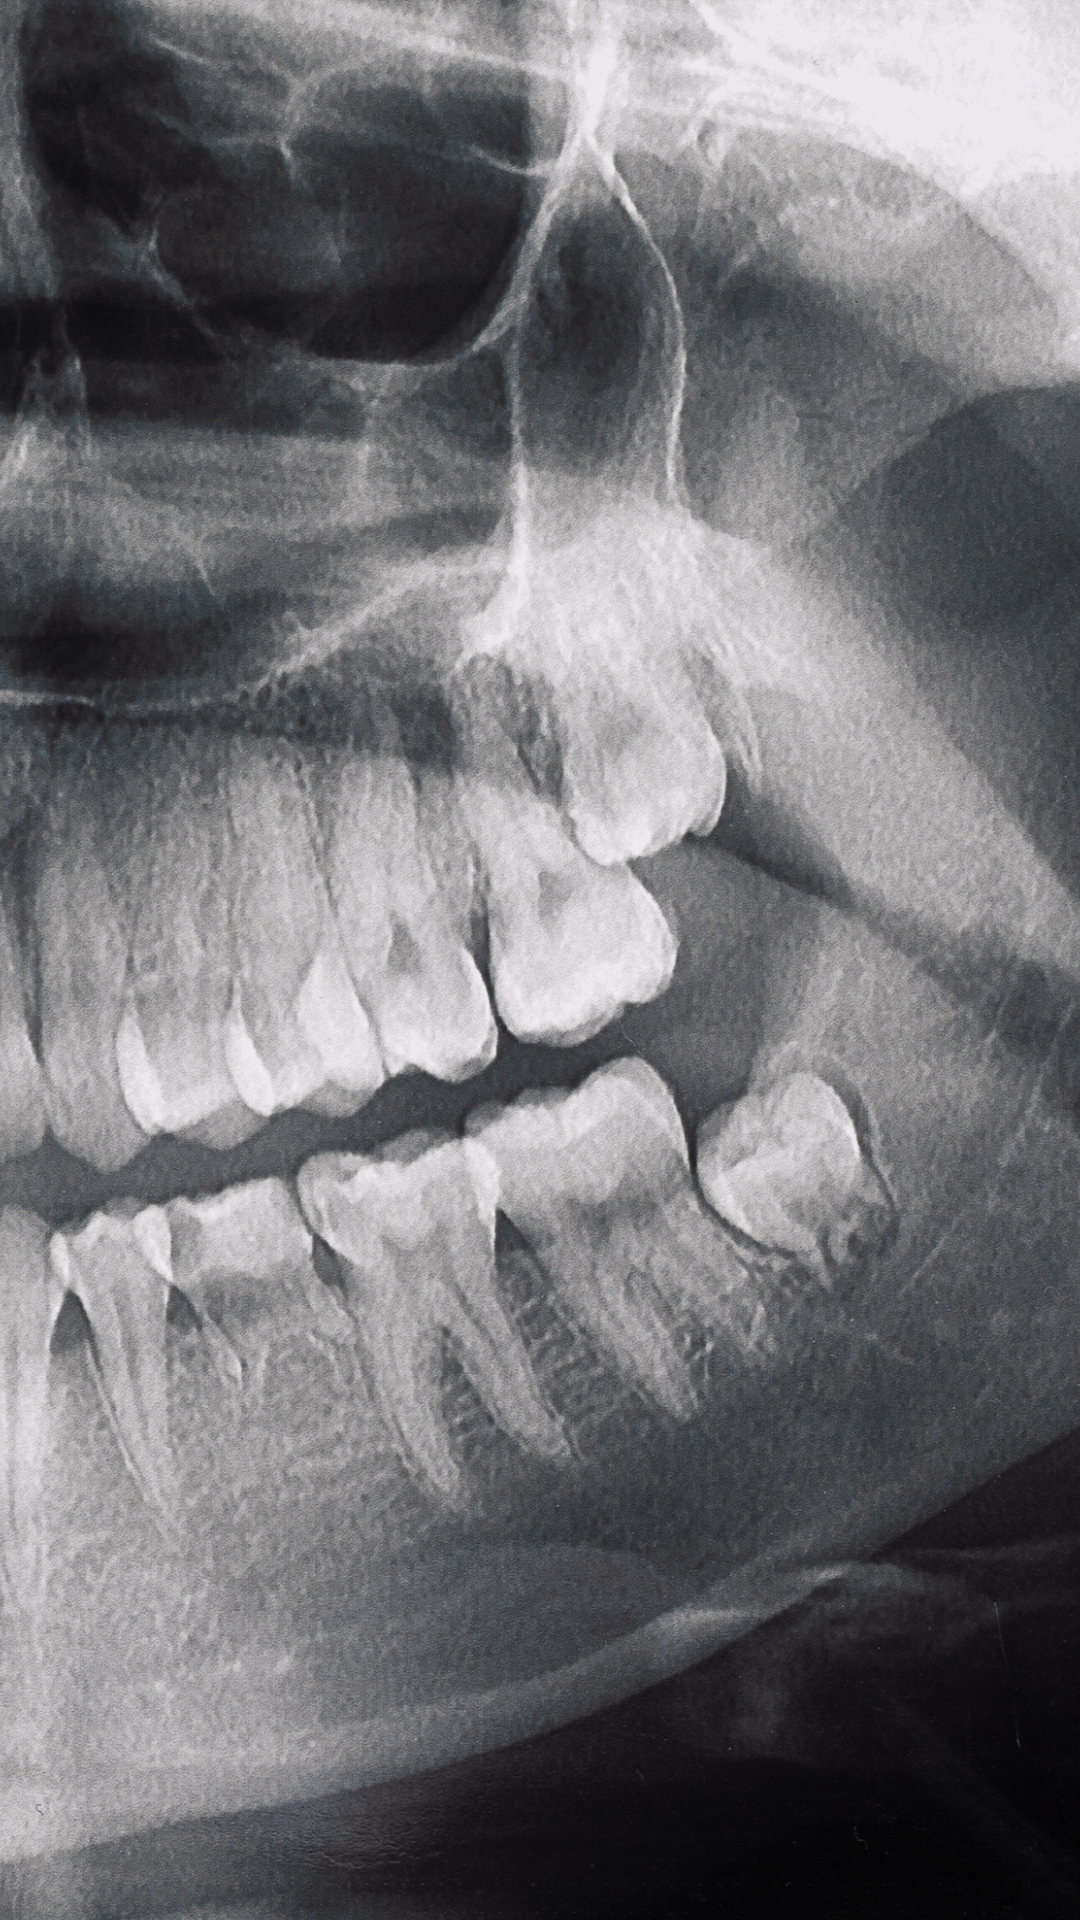

¿Necesitas imágenes tridimensionales precisas? Nuestras tomografías 3D te brindan diagnósticos milimétricos para planificación de tratamientos.